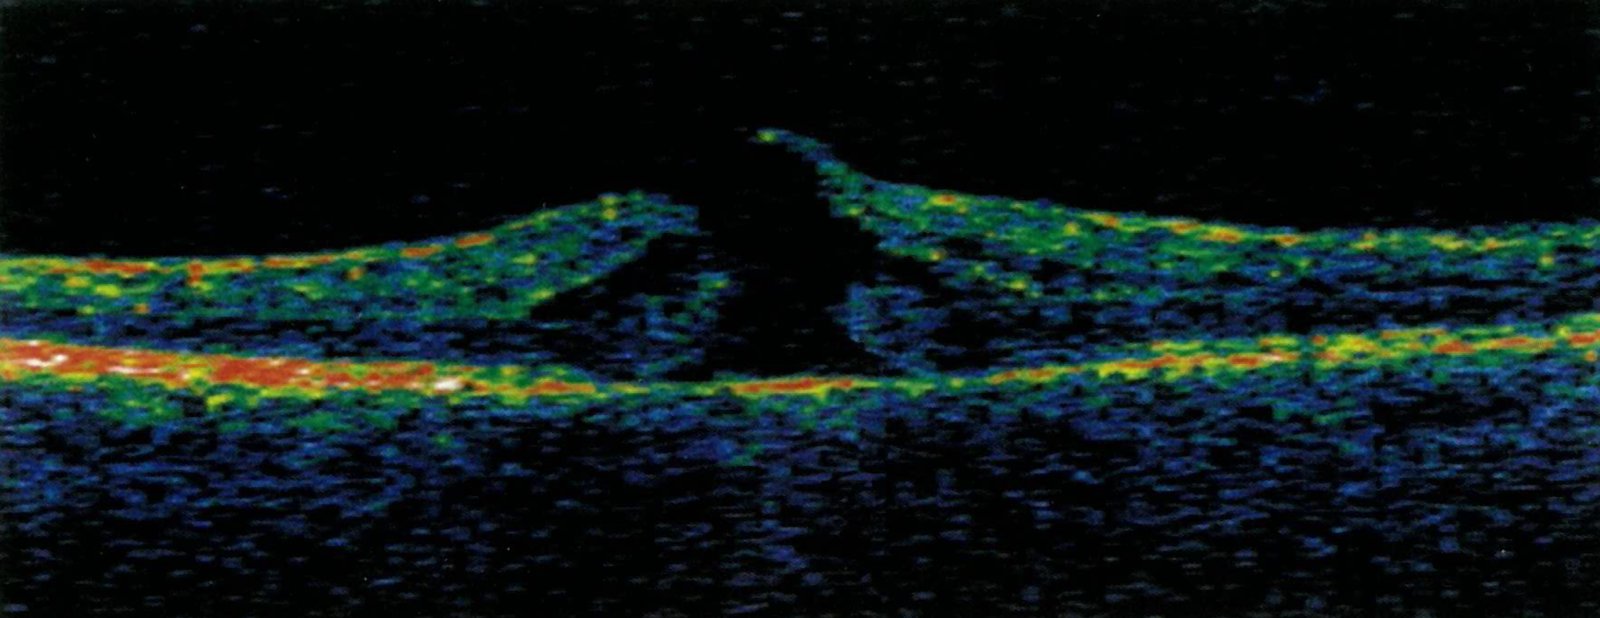

Diabetic retinopathy (dieuhBETik retihNOPuhthee) is a diabetes complication that affects eyes It's caused by damage to the blood vessels of the lightsensitive tissue at the back of the eye (retina) At first, diabetic retinopathy may cause no symptoms or only mild vision problems Eventually, it can cause blindnessJohn Milton's career as a writer of prose and poetry spans three distinct eras Stuart England;A shadow or dark curtain describes when vision is decreased or partially blocked by dark or grey shapes moving across or in the side of the visual field Shadow or Dark Curtain in Vision may be associated with In many cases, blindness and vision loss are preventable

Detached Retina Overview And More